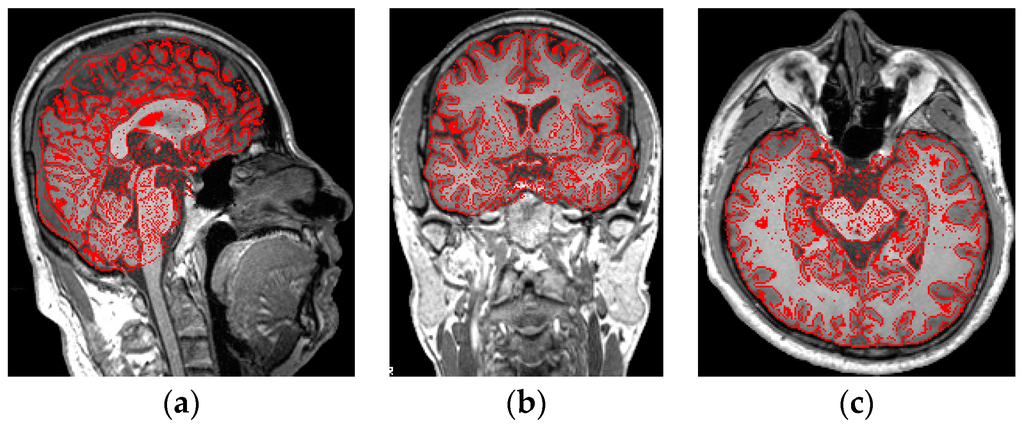

2. Materials

3. Preprocessing